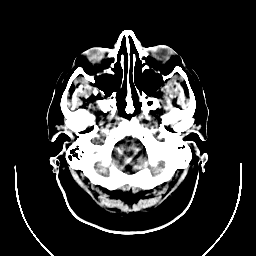

CT Study #1 -- Slice #3

[Home][Help][Clinical][Tour 1] Slice 3